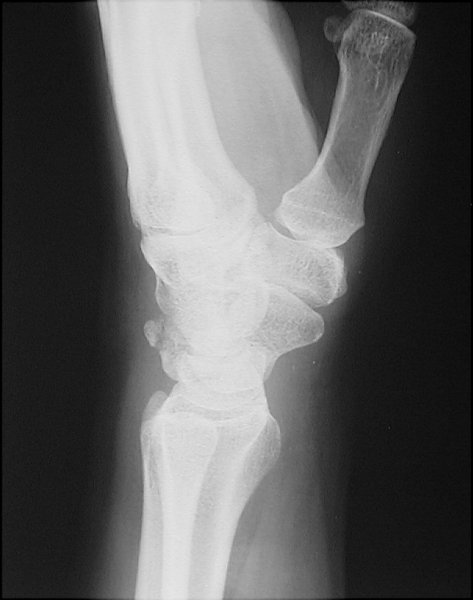

Return to Triquetral Fracture